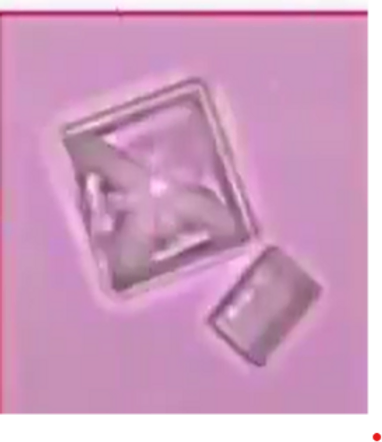

Comparison of crystals in the blood and in the vaccine; on the left, crystalline formations are found in the blood of test subjects vaccinated with Comirnaty (BioNTech/Pfizer), the images on the right show that these types of crystals are also found in Comirnaty vaccines. Image credit: Helen Krenn

Graphene Ferric oxide crystals (Ferromagnetic Properties) and Trypansoma cruzi parasite eggs were observed in the live capillary blood from a VAXXinated male using Brightfield, pHase contrast microscopy and confirmed with UV absorbance and Fluorescence Spectroscopy, Scanning Electron Microscopy, Transmission Electron Microscopy, Energy Dispersive Spectroscopy, X-ray Diffractometer and Nuclear Magnetic Resonance instruments. – Copyright Hikari Omni Media – Robert O. Young MSc, DSc, PhD, Naturopathic Practitioner – 2021